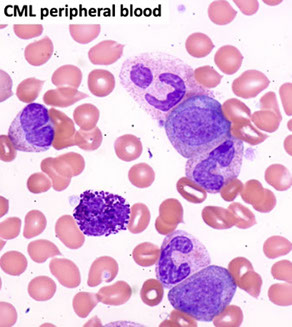

Chronic myeloid leukemia (CML), BCR-ABL1 positive

Leukocytosis, with immature and mature cells. Thrombocytosis is common, S-megaly from EMH

- can be dx'd from PB, but should get BM to ensure enough material for KT and confirm phase of dz

Sx: Fatigue, shortness of breath on exertion, malaise, fullness of upper abdomen, anorexia and weight loss, priapism: due to extremely elevated WBC or platelet count.

Peripheral Blood Lab Findings:

Marked leukocytosis (50 - 600 X 10^9/L). Basophilia. and eosinophilia

Thrombocytosis.

Anemia is normochromic normocytic.

Elevated serum vit B12 and vit B12 carrying capacity

- Decreased leukocyte alkaline phosphatase (LAP)

Chronic Phase (CP)

Leukocytosis w myelocytes and segs. Eosinophilia common

- blasts ususally <2% on PS

CML- chronic phase PB